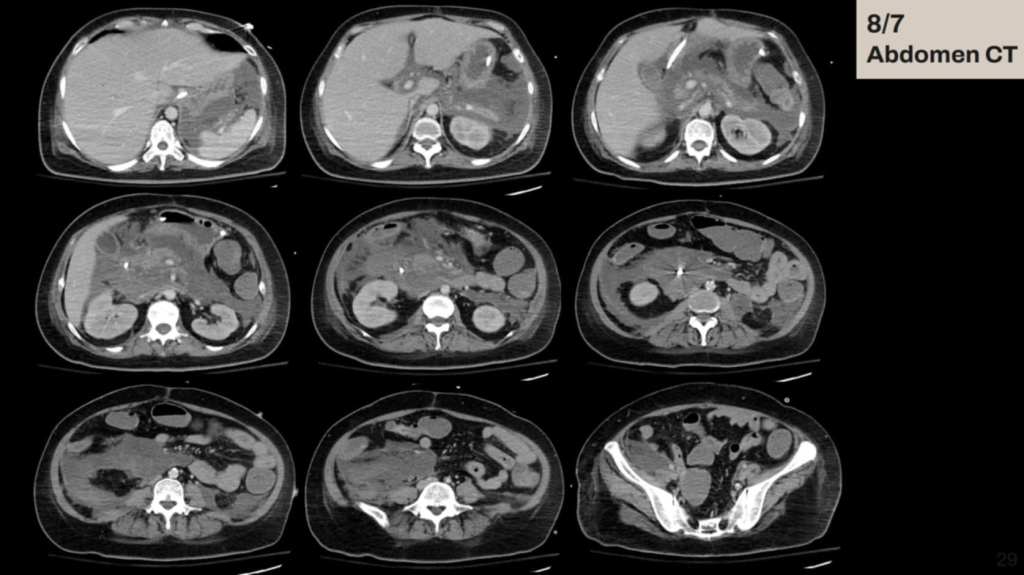

這次的主訴是腹、腰和背痛,合併頭暈嘔吐,在急診vital sign穩定,PE也沒有specific finding(包括abdominal tenderness, rebounding pain等),抽血看到TG 8000多、lipase 1000出頭。在急診的第三天休克,發燒和心跳快,當時使用了levophed等升壓藥並切了CT,看到grade E, CTSI 6的acute pancreatitis,隨後住進加護病房進行處置。